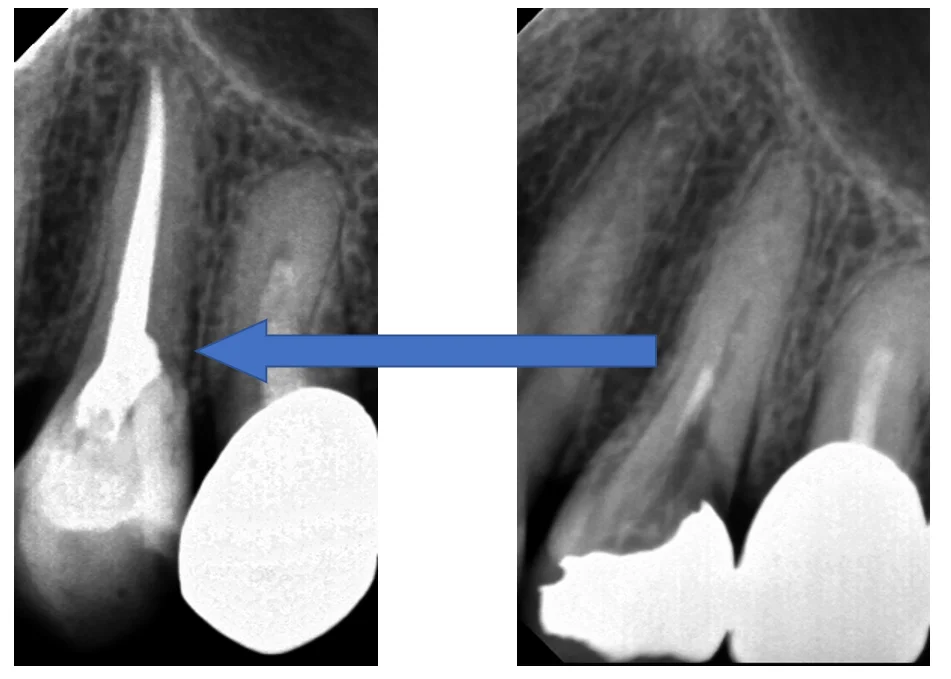

ちなみに、本来あるべき根の形としてはこういったものになるはずなんです。

最初の画像と見比べてもらうと根の管がどれだけ見えづらくなっているのかが分かると思います。

詰めたレントゲンがこちら。

実は途中で根の管が分岐していて・・・それでいてイスムスがあったので、その分岐した根管を更に削って大きな一本の根にしました。

イスムスというのは二つの根の間にある狭い交通路のようなもので、これが細菌繁殖の原因にもなりかねない危険なものです。

太さは0.1mmも無いので、よく見逃されていますが、その結果根の先に膿が溜まってしまいます。

術前術後がこちらですね。

根の先まで隙間なくしっかりと詰まっていて、最初のちょろっとしか入っていなかった薬に比べると随分としっかりと入ったのが分かると思います。